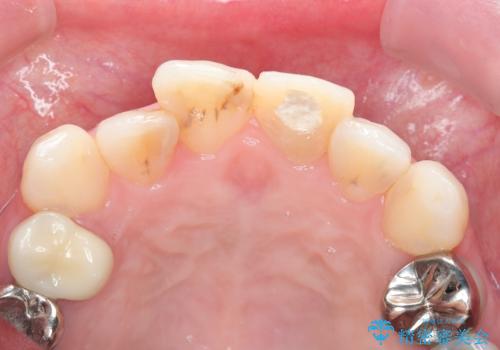

- 自転車で転倒してしまい、前歯を折ってしまい、痛みと見た目の改善を希望され来院されました。

もともと根管治療の為されて歯が折れてしまっているので、根管治療を行い審美的なセラミック治療を行う治療計画としました。

- 15.4万円(ジルコニアクラウン・仮歯・ファイバーコア)費用は治療当時の料金となります